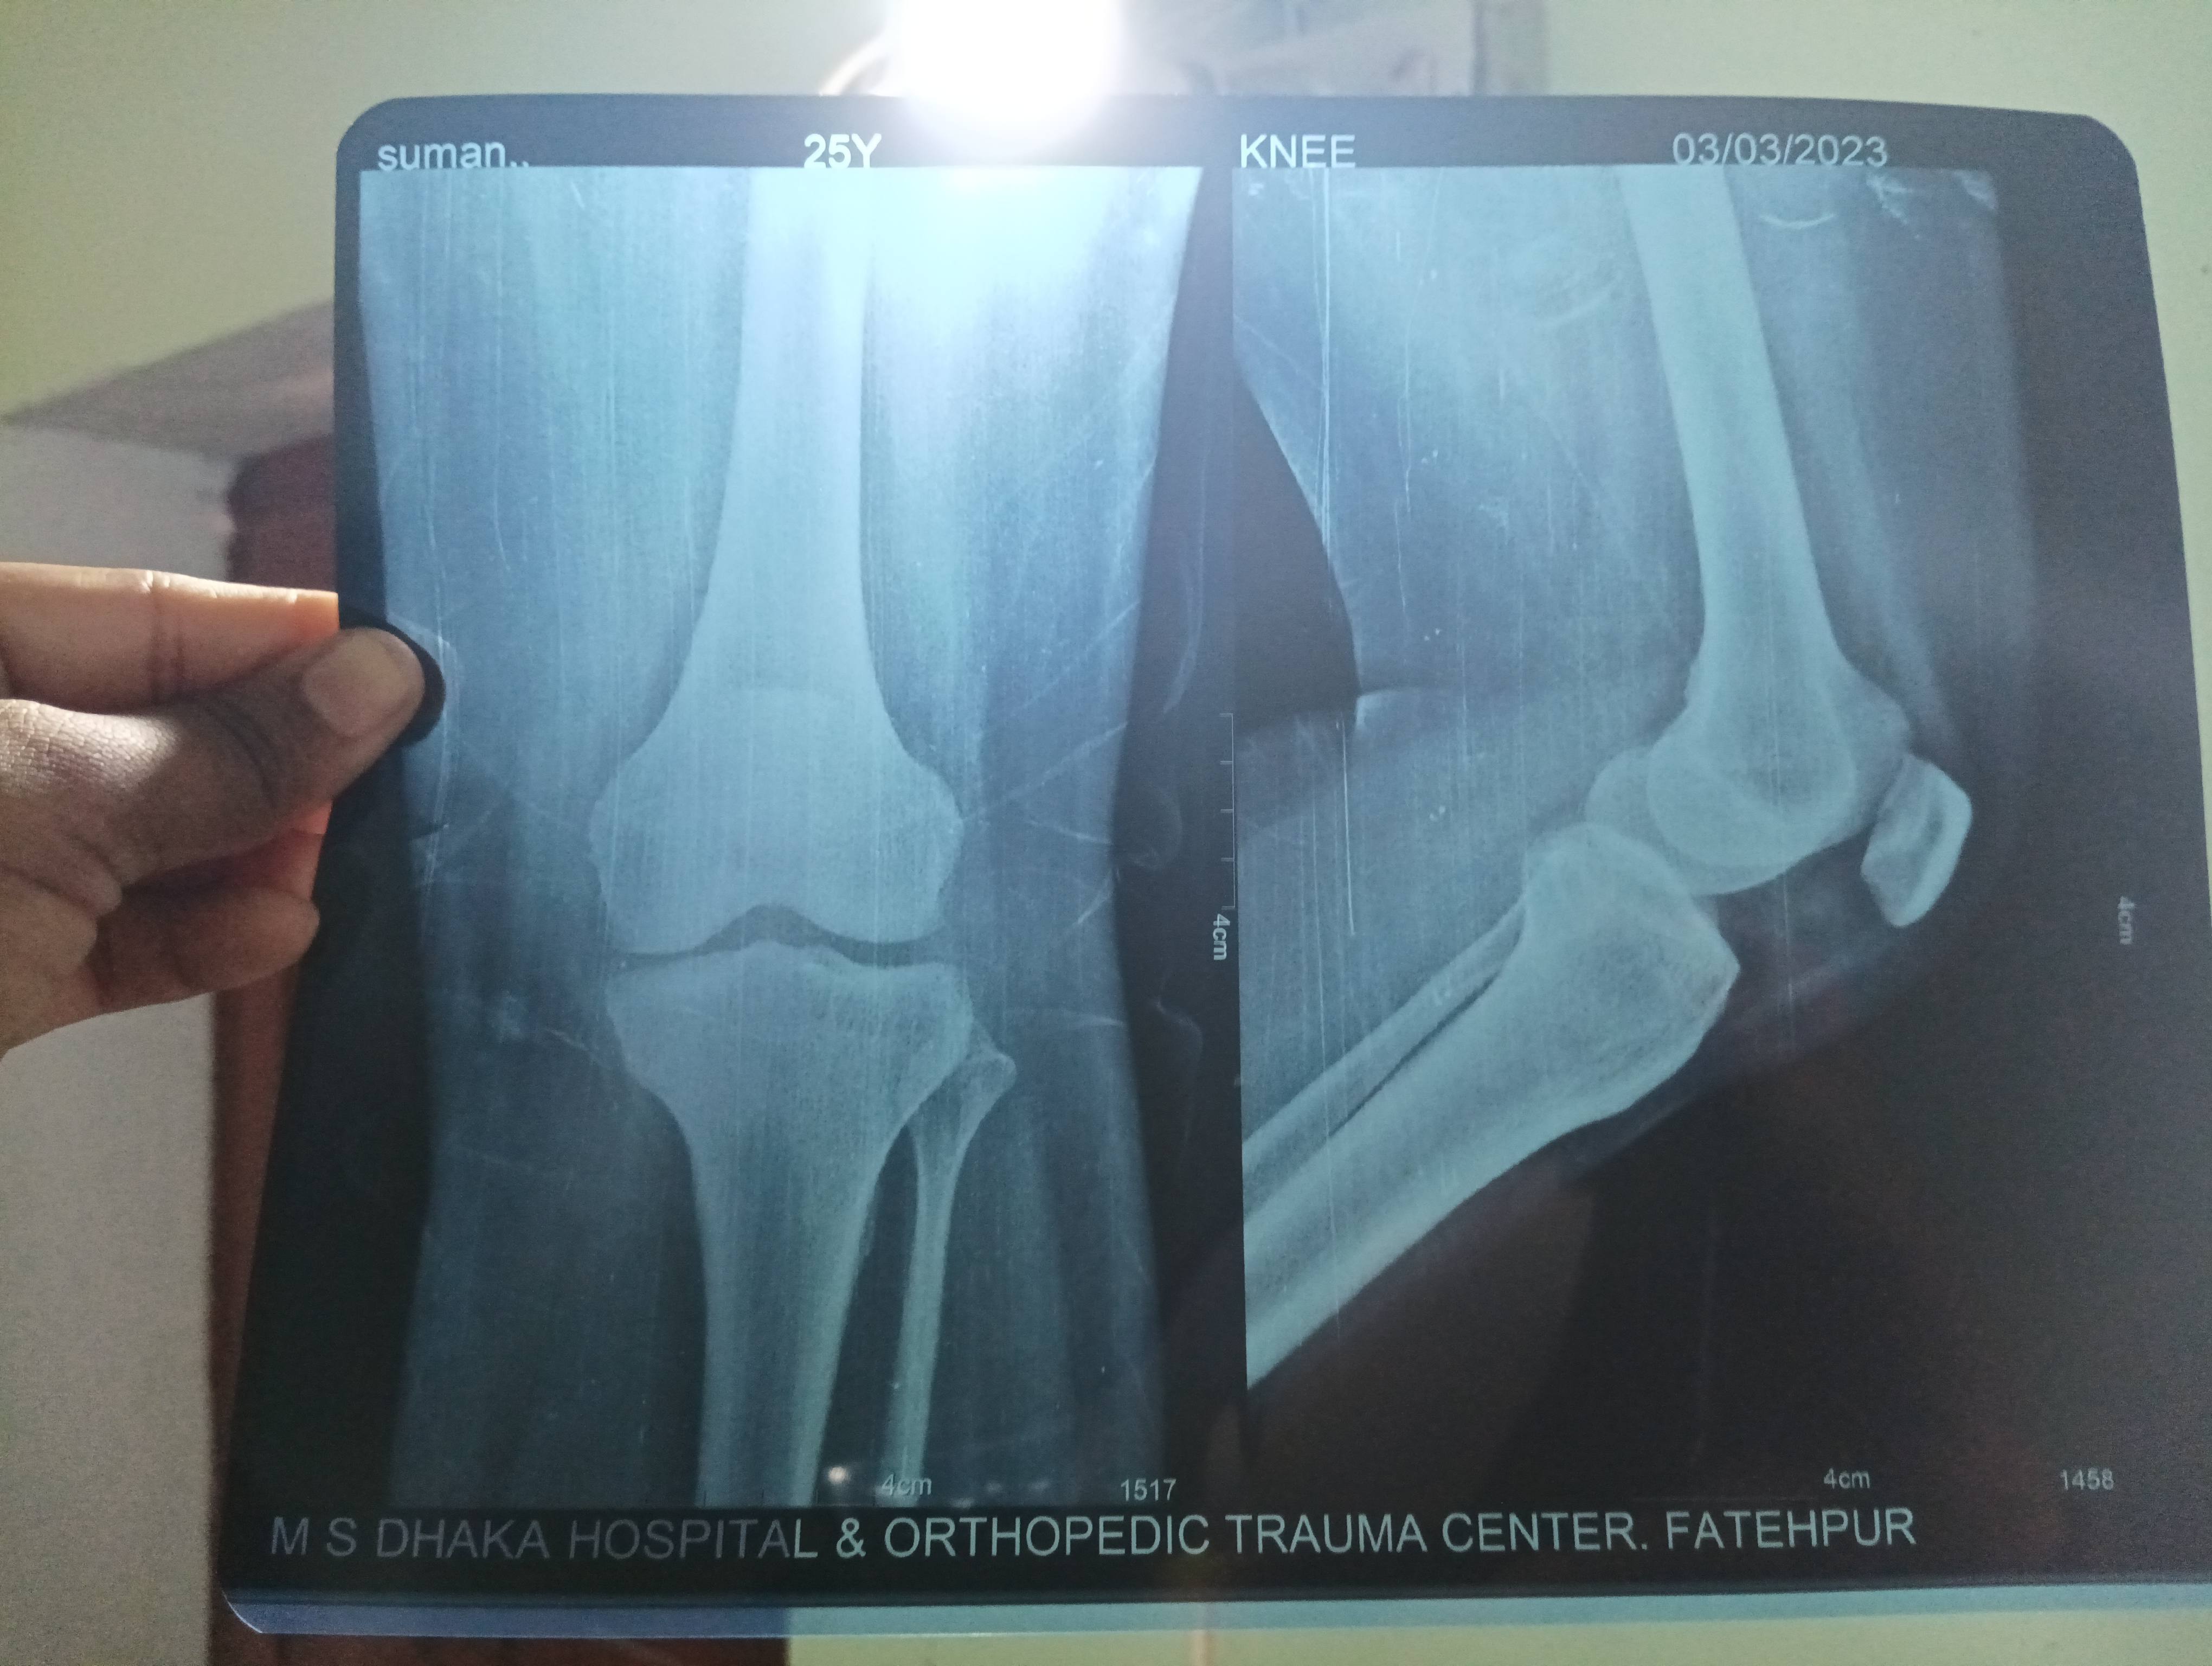

Sir plz btaye kya problem h

Sir ek mhine phle andr ki said gutna nikla tha but abhi tk chlne pr drd hota h

Iska mri TEST karwana sahee rahega